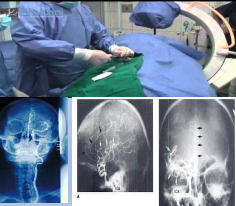

• Arteriogramas Cerebrales Biplano.

• Cateterismos Cardíacos: adultos ( Angio y Cine 35 mm.) Pediátricos (Angio Biplano y Cine de 35 mm.)

• Art. Cerebrales, Neumoencefalografías.

• Melografías